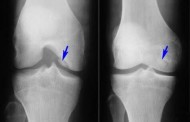

| Рентгенография | Состояние костей, наличие деформаций, сужение суставной щели | При первых жалобах на боль и ограничение подвижности |